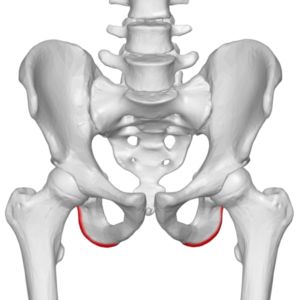

If you’ve spent any time on a picnic bench, you understand all too well what part of the body gets sore. The sitting bone, the ischial tuberosities, which is at the bottom side of the ischium, shown in the diagram to the right.

If you’ve spent any time on a picnic bench, you understand all too well what part of the body gets sore. The sitting bone, the ischial tuberosities, which is at the bottom side of the ischium, shown in the diagram to the right.